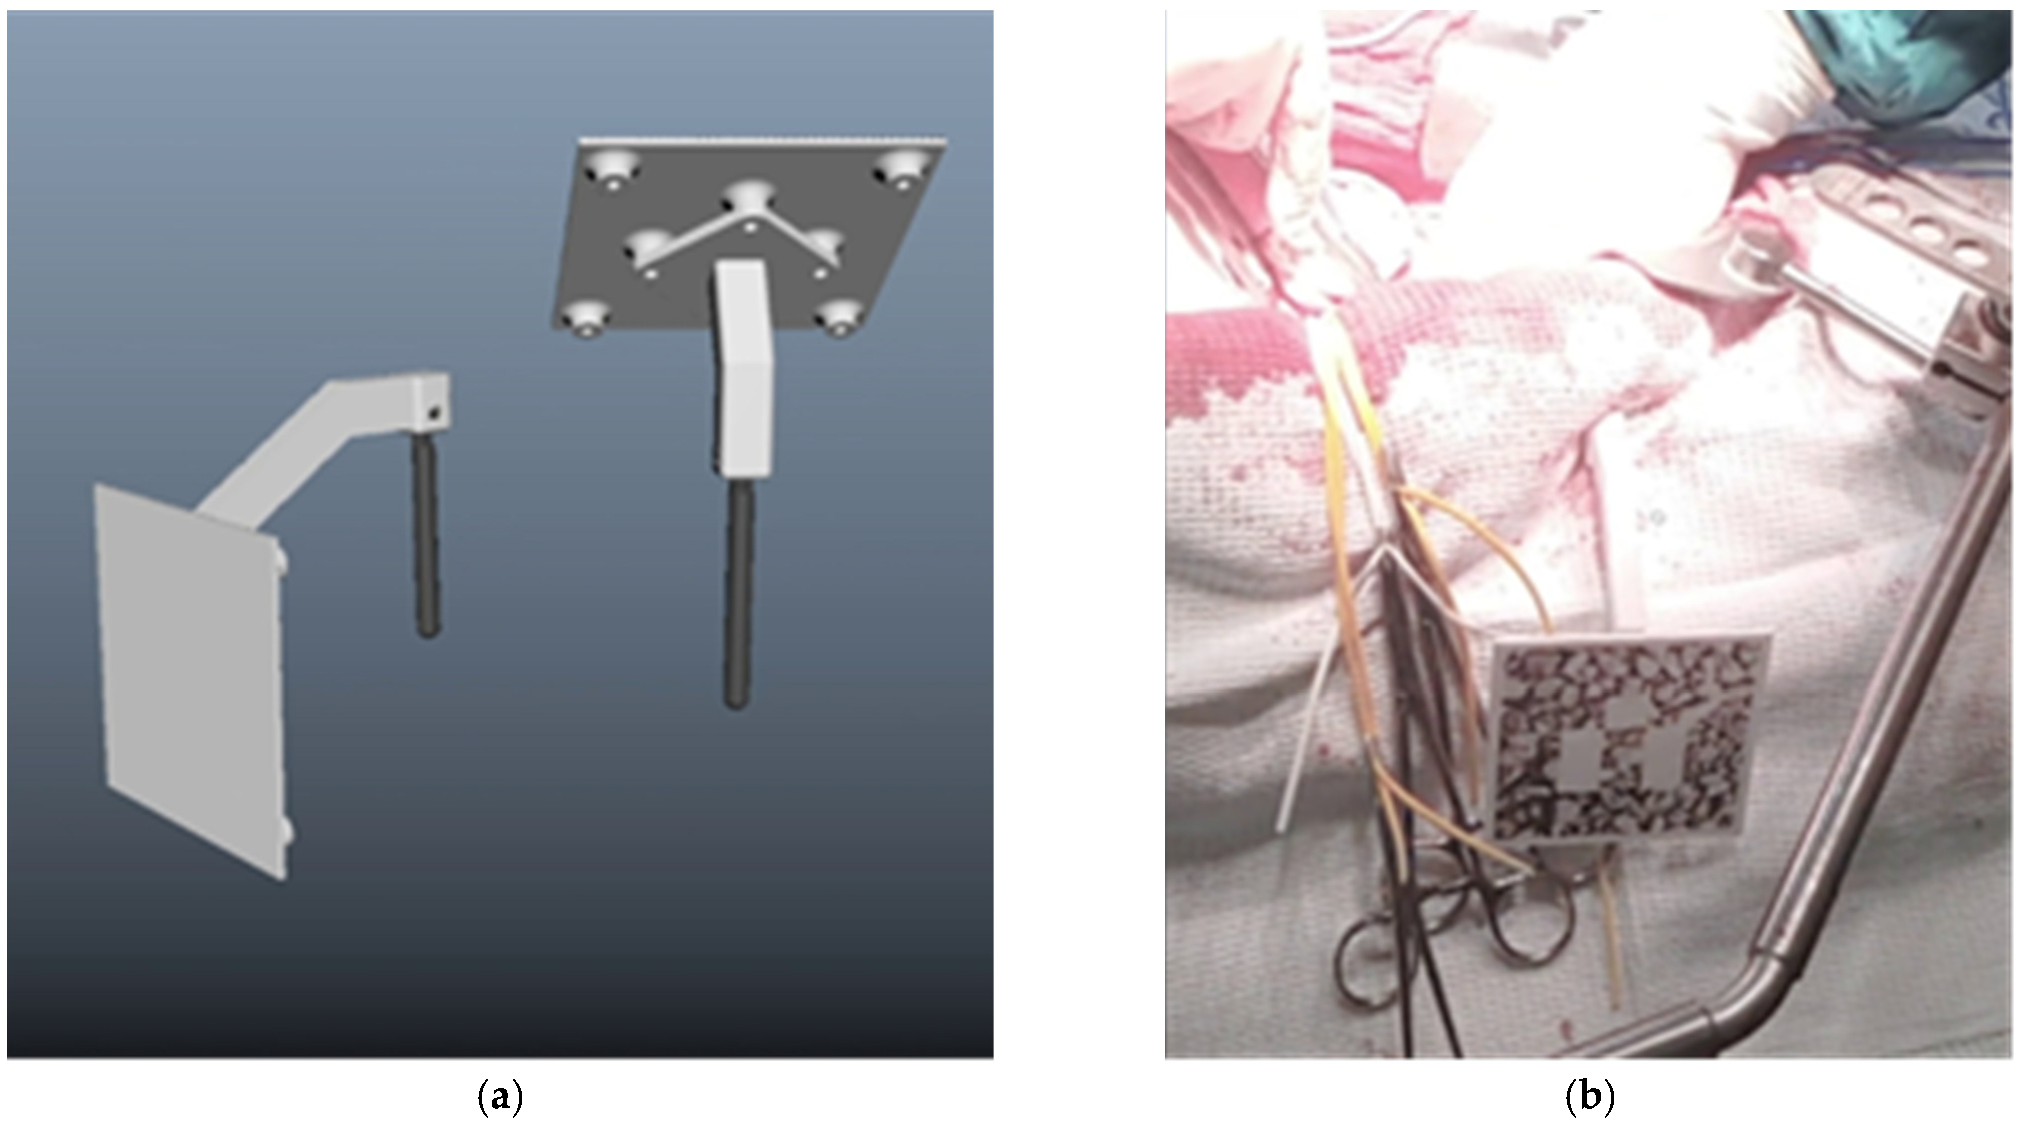

3.1. Clinical Experience in Cases with Invasive Markers

- Bone fixation of a marker

- Two (or more) marker design for position changes

- Magnet fixation of a marker